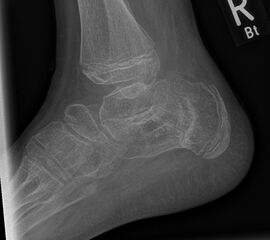

Diagnostisches Vorgehen

Damit die minimalinvasive Fußchirurgie zur Korrektur kindlicher oder jugendlicher Fußdeformitäten erfolgreich angewendet werden kann, erfordert die präoperative Diagnostik Röntgenbilder in drei Ebenen am stehenden Fuß. Röntgenbilder ohne Belastung des Fußes sind nicht zielführend. Im Fall von schweren Rückfußdeformitäten wird das obere Sprunggelenk in die radiologische Diagnostik mit einbezogen in Kombination mit der Rückfußaufnahme unter Belastung („Saltzman View“). Das OSG wird in zwei Ebenen geröntgt. Die streng seitliche Aufnahme des OSG kann bei den komplexen Fußdeformitäten mit der seitlichen Aufnahme des Fußes unter Belastung kombiniert werden. Das reduziert die diagnostische Strahlenbelastung der Kinder.

Indikationen für die beschriebenen Röntgenaufnahmen sind Klumpfußdeformitäten zur Beurteilung eines „flat top talus“ oder neurologische Grunderkrankungen mit varischer Fersenstellung wie zum Beispiel bei HSMN (Hereditäre Sensorische Motorische Neuropathie).